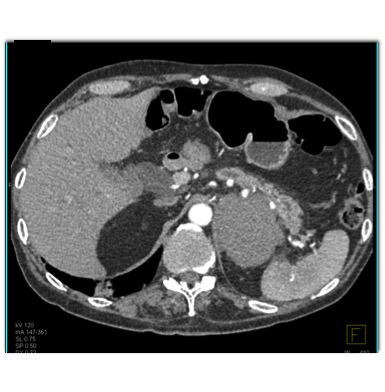

The most likely diagnosis in this case is

pancreatic cancer

lymphoma

primary adrenal cancer

paraganglioma